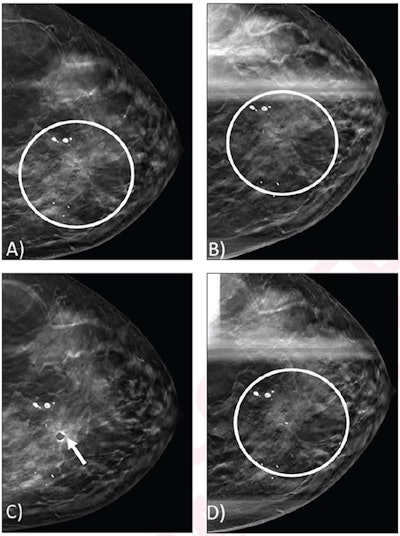

(A) Craniocaudal view from screening DBT mammogram shows architectural distortion (circle) in the upper inner position, which was not detected by digital mammography (not shown). (B) Spot craniocaudal view from subsequent diagnostic DBT mammogram shows persistence of architectural distortion (circle). No ultrasound correlate was identified (not shown). Core needle biopsy of the architectural distortion was performed, yielding a radial scar without atypia. (C) Post-biopsy mammogram shows cylinder clip (arrow) in appropriate position. Biopsy result was considered concordant, and patient underwent recommended imaging surveillance. (D) Spot craniocaudal view from diagnostic mammogram performed 12 months later shows stable appearance of an architectural distortion (circle).ARRS